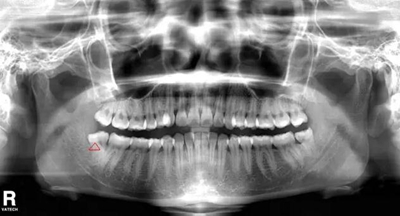

智齒遠(yuǎn)中阻生(遠(yuǎn)離鄰牙方向長(zhǎng))反復(fù)炎癥感染

2.jpg